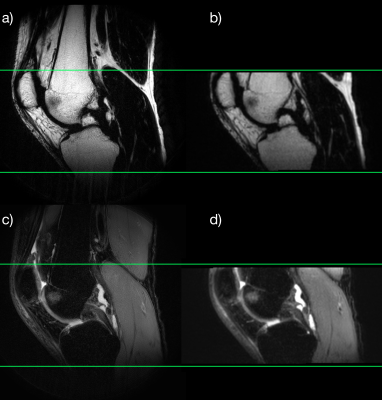

Resulting images (Figure 2) show that high quality reformattable fat/water separated volumes can be acquired with an SMS accelerated PROPELLER sequence in a reasonable time frame. A small area of subchondral bone marrow edema of the volunteer was clearly visualized in all three planes. Figure 3 compares a sagittal pseudo 3D reformat to a high resolution image acquired in the sagittal plane, showing the reformat quality achievable with 1 mm slices.

Figure 3: Right knee. A comparison of the sagittal reformats (b & d) to high resolution regular 2D images (a & c). Green lines show the extent of the FOV in the regular images.